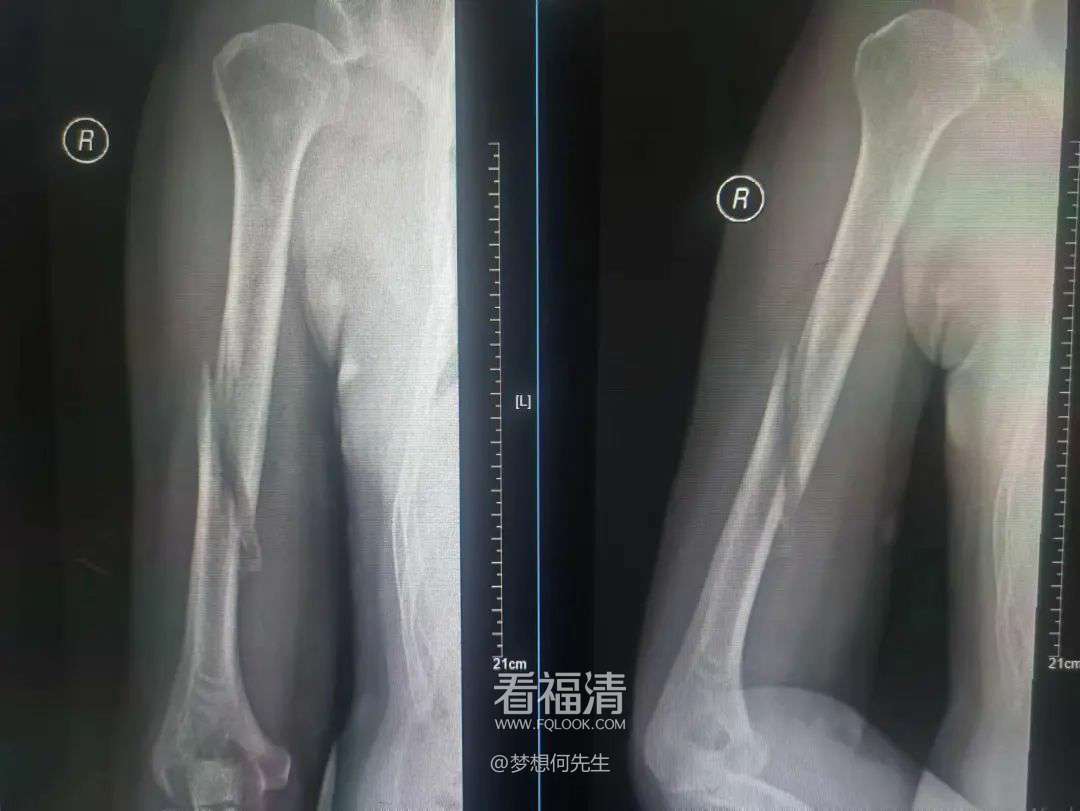

伤后43天拍片

伤后43天,患者再次接受拍片复查。这次的结果令人欣喜,骨折块贴合良好,且已有少量骨痂生长。根据这一进展,王征勇指导患者戴着小夹板开始主动进行肩关节功能锻炼。这不仅有助于骨折的愈合,还能加速患者上肢功能的恢复。

2个多月后拍片

在伤后近2个月的随访中,患者再次接受拍片复查。结果显示,骨折对位对线依然良好,且已有大量骨痂生长。这一显著的进步让王征勇决定为患者拆除外固定装置,以便他能更加自如地进行康复锻炼。

6个月后拍片

最终,在伤后近6个月的复诊中,患者恢复良好,已完全恢复正常生活。